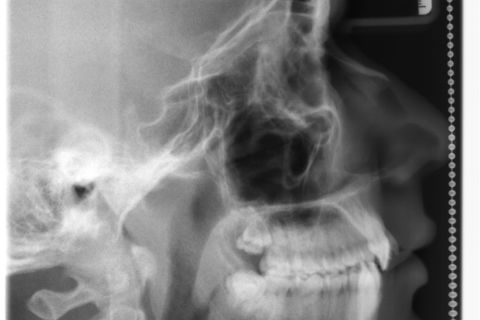

Inicial Rx Cef.

Paciente: Sexo masculino, 16 anos

Diagnóstico: Classe II, divisão 2

Sugestão de Tratamento: Tratamento ortodôntico com o uso do sistema de alinhadores removíveis Invisalign. Sem extrações dentarias, pois o perfil do paciente não era favorável. Por ser um paciente jovem, optou-se por uma expansão dentária controlada, buscando a remodelamento dos arcos.